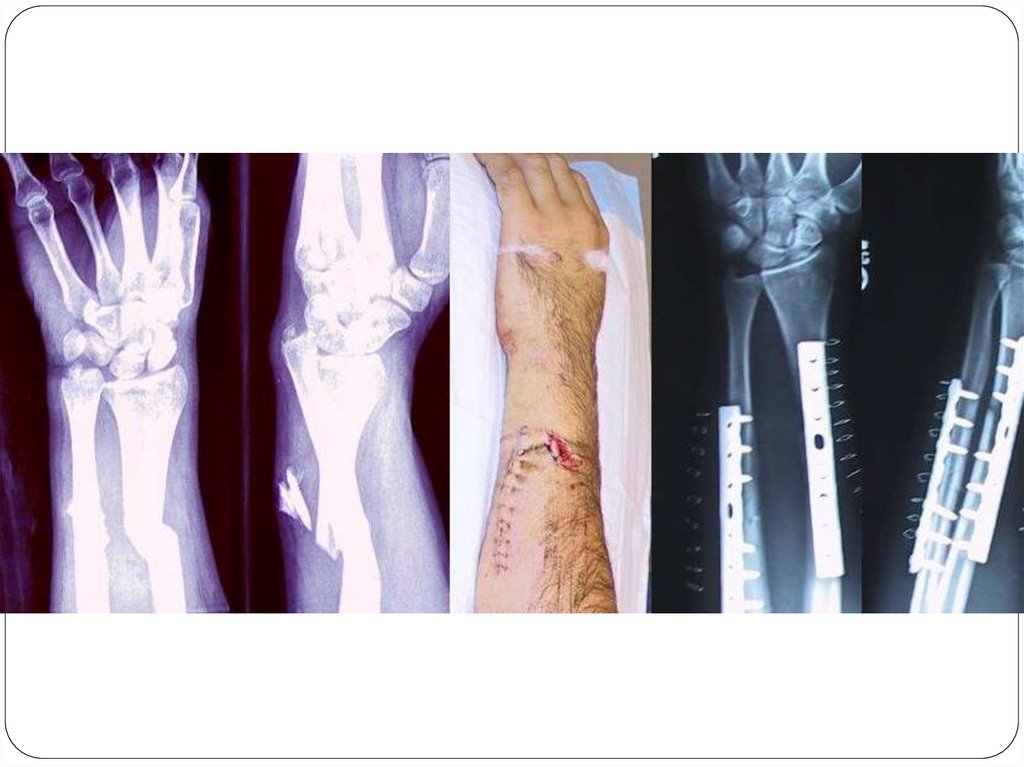

ОПЕРАТИВНОЕ ЛЕЧЕНИЕ ПЕРЕЛОМОВ

Оперативное лечение перелома

предусматривает одномоментную

открытую (чаще) или закрытую (реже)

репозицию костных отломков и их

прочную фиксацию – остеосинтез.

Различают 2 основных вида

остеосинтеза:

внутренний (погружной) с

помощью спиц, винтов,

штивтов.

наружный – аппаратами

внешней фиксации (аппарат

Илизарова)

Виды погружного остеосинтеза:

Кортикальный остеосинтез – фиксация путем

проведения винтов или спиц через оба

кортикальных слоя кости после открытой

репозиции отломков. Показан при переломах костей

с большой плоскостью соприкосновения отломков

(косые, винтообразные).

Накостный остеосинтез – фиксация отломков

осуществляется при помощи пластины,

закрепляемой винтами на поверхности кости.

Интрамедуллярный остеосинтез - фиксирующую

конструкцию (гвоздь, стержень, штифт) вводят в

костно-мозговой канал.